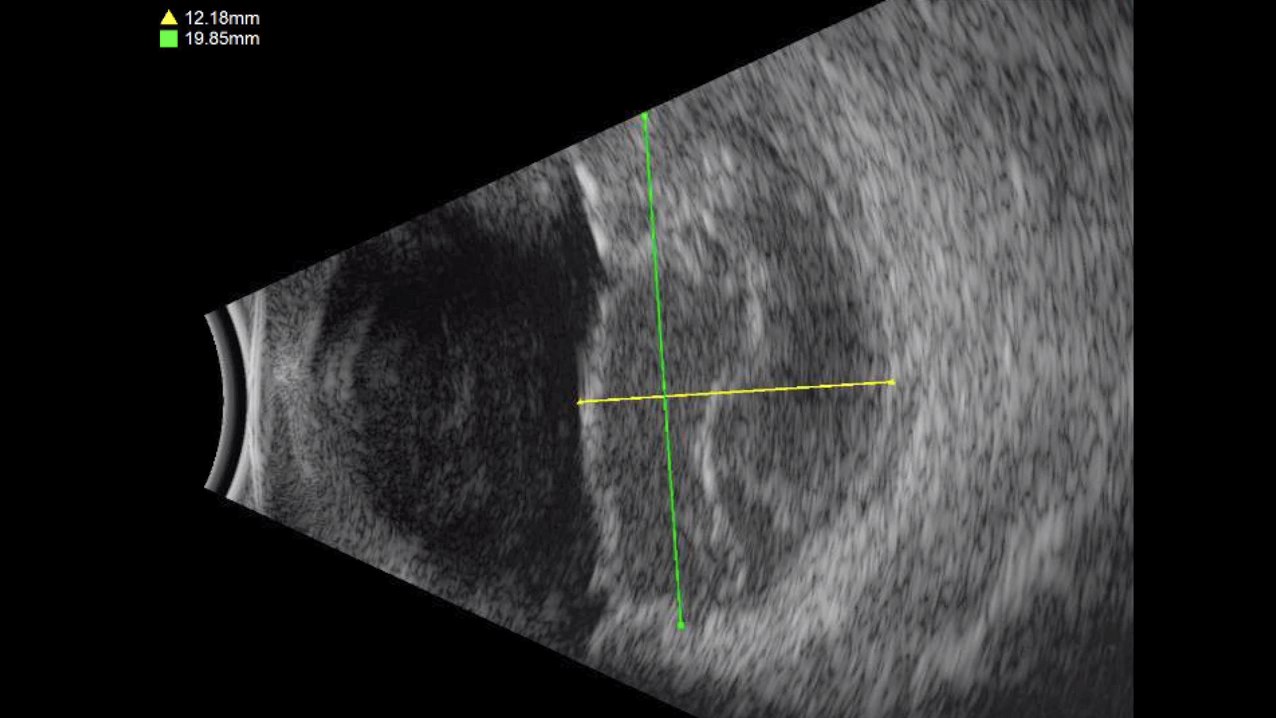

Myopic Macular Hole

Jose Garcia Arumi, MD

Stretched Macula

Stratos Gotzaridis, MD

High Myopia and Macular Hole

Patricia Udaondo, MD